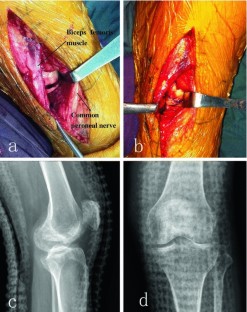

Fig. 2